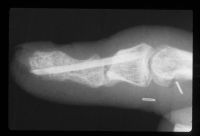

| Case 1. This patient presented with a progressive index finger nail deformity years after an open crush injury of that fingertip. |

| Xrays show loss of much of the distal half of the distal phalanx, with cortical disruption. |